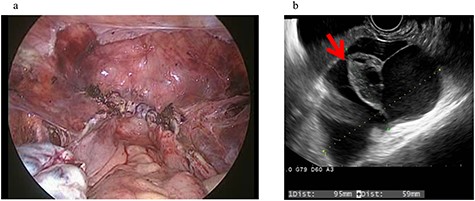

A 43-year-old woman, gravida 2, para 2 was diagnosed with uterine myoma and underwent TLH. No abnormal intra-abdominal findings, such as adhesions, endometriosis or ovarian cysts, were detected. As shown in Fig. 2a, no abnormal findings, such as adhesions, were detected at the end of surgery or 2 months later.

Clinical findings of case 2 (before surgery for PIC). (a) Findings at the end of TLH. No abnormal findings were detected. (b) An US image of PIC. The major axis was 95 mm. An ovary with a normal appearance was observed within the multilocular cyst.

Four years and 6 months after surgery, she presented with lower left abdominal pain. A multilocular cyst, measuring ~10 cm, was detected on the vaginal stump by transvaginal US (Fig. 2b). Since the cyst was considered to be causing her symptoms, emergency surgery was performed. Adhesions were observed in the left adnexal region, and a clear yellow liquid was retained in the cavity formed by the adhesions (Fig. 3). The adhesions were removed by laparoscopic surgery and left adnexal excision was performed, which ameliorated her symptoms.